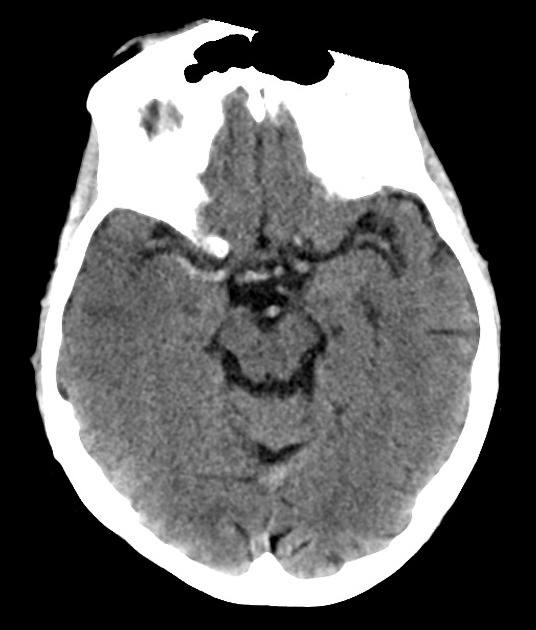

Nhồi máu não

» Thông tin: Nam giới – 60 tuổi.

» Lâm sàng: Đau đầu + Liệt nửa người trái / NIHSS 18 điểm.

# Nhồi máu sớm bán cầu phải thuộc vùng cấp máu ĐM não giữa / Huyết khối ĐM não giữa phải.